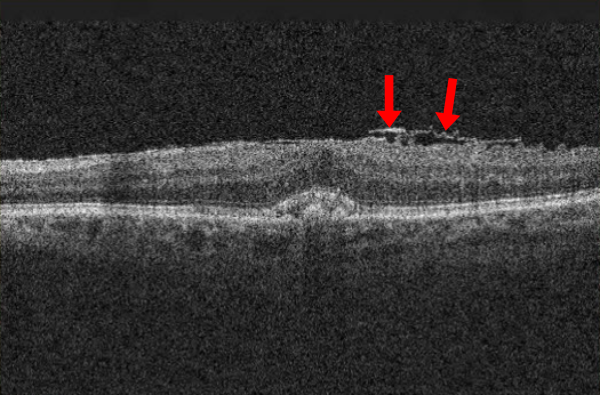

- Оптическая когерентная томография — основной метод диагностики и динамического наблюдения — позволяет увидеть изменения в слоях сетчатки и оценить влияние ЭРМ на анатомию сетчатки.